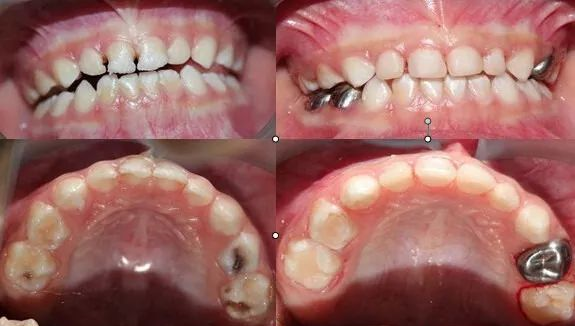

Part.2 哪些患牙需要做预成冠?

乳磨牙龋坏的高风险儿童;广泛龋坏、大面积龋损或者多个牙面龋损的患牙;进行牙髓摘除术或冠髓切除术的患牙;某些矫治器的基牙等。

儿童牙医建议:儿童牙齿萌出后,家长们应注意多观察儿童的牙齿生长状况,发现牙齿龋坏或其他问题应及时到口腔医院进行检查与治疗。为保护儿童的乳牙,我们倡导进行乳磨牙金属预成冠。